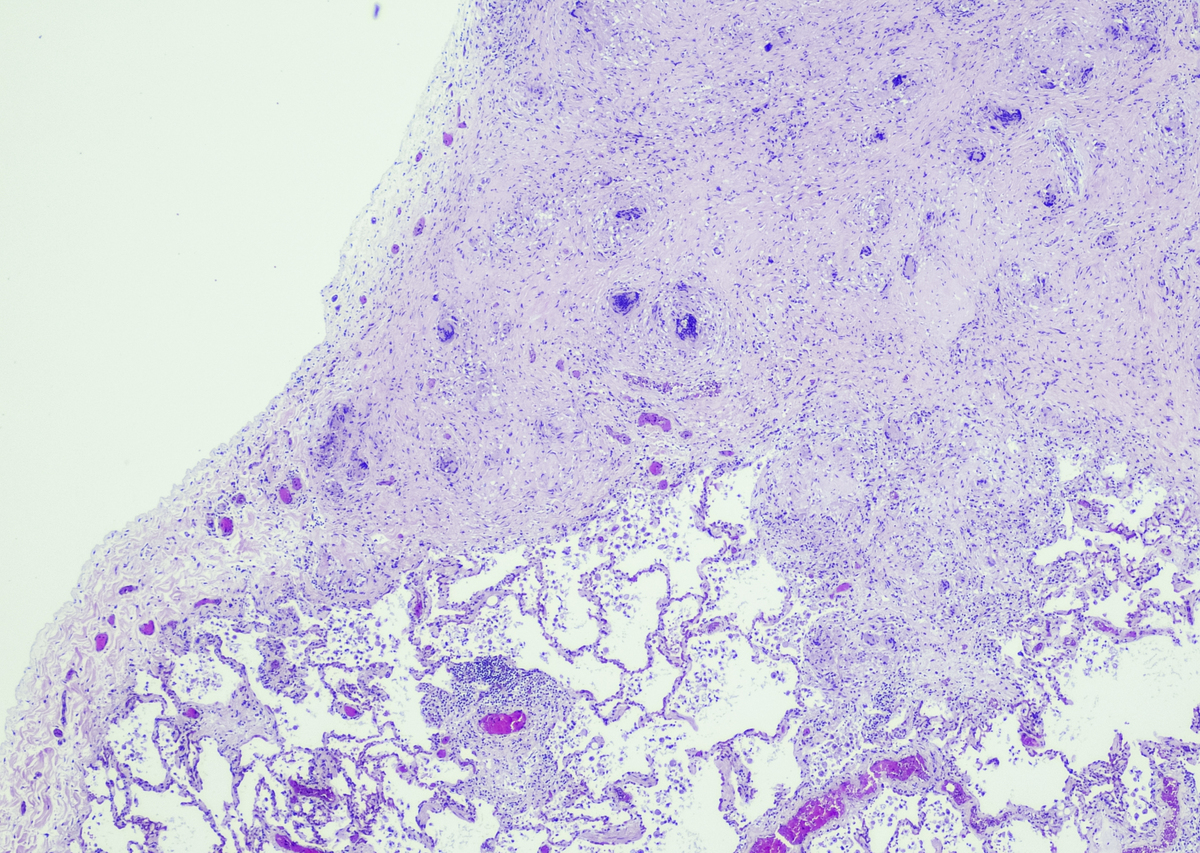

根据提供的信息,肿瘤细胞CK(+)表示肿瘤细胞表达细胞角蛋白,EP-CAM(+)表示肿瘤细胞表达上皮细胞肿瘤标志物,SSTR2部分(+)表示肿瘤细胞部分表达生长抑素受体2,INSM1(-)表示肿瘤细胞不表达INSM1,Syn(-)表示肿瘤细胞不表达突触素,CgA(-)表示肿瘤细胞不表达嗜铬粒蛋白A,CD56部分(+)表示肿瘤细胞部分表达CD56,TTF-1(-)表示肿瘤细胞不表达甲状腺转录因子-1,NapsinA(-)表示肿瘤细胞不表达Napsin A,P63(-)表示肿瘤细胞不表达P63,P40()表示P40的表达情况未提供,LCA(-)表示肿瘤细胞不表达白细胞常规抗原,Ki67约70%(+)表示肿瘤细胞的增殖指数约为70%。综合分析这些标记物的表达情况,可以帮助医生确定肿瘤的类型和特征,从而指导治疗和预后评估。

肿瘤细胞免疫组化标记物分析:CK(+)、EP-CAM(+)、SSTR2部分(+)、INSM1(-)等